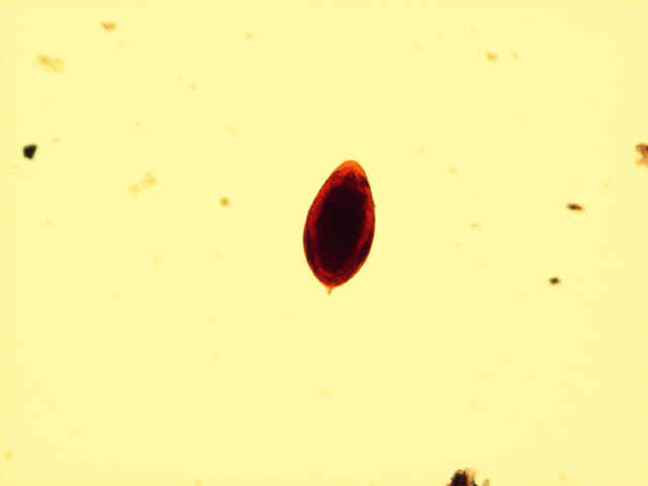

Schistosoma Mansoni